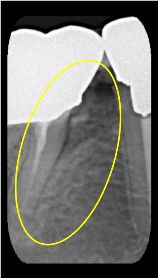

垂直性骨吸収+α-TCP

Perio Wave +Er:YAGレーザー+コールドレーザーの例です。

Perio Wave+Er:YAGレーザー+コールドレーザーで治療した箇所の経過です。

左から直後、1ヶ月経過時、2ヶ月経過時の画像です。